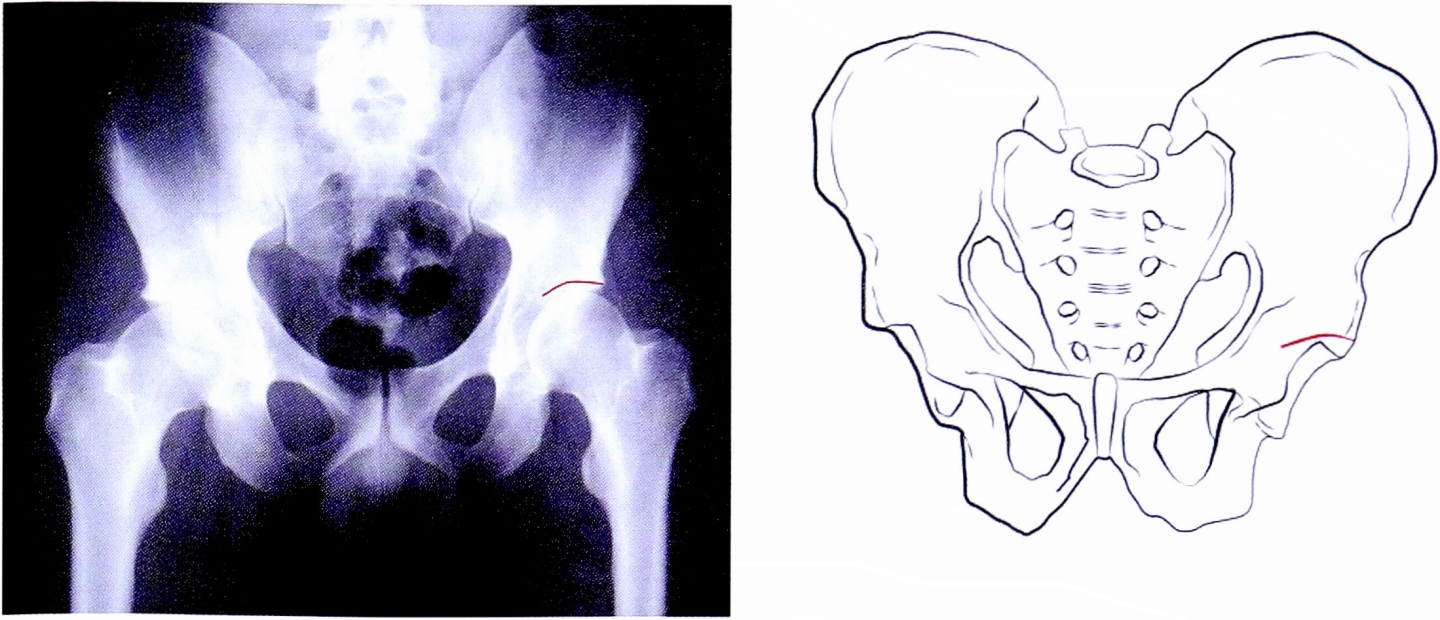

- Подвздошно-гребешковая линия (соответствует терминальной линии тазового кольца) в передних отделах соответствует передней колонне вертлужной впадины, в задних отделах она отражает тело подвздошной кости на протяжении до крестца — в норме она непрерывна (рис. 1). С клинической точки зрения целостность тазового кольца определяет непрерывность подвздошно-гребешковой линии.

Рис. 1. Подвздошно-гребешковая линия на рентгенограмме и на схематическом изображении таза.

Fig. 1. Ileopectineal line on AP pelvic X-ray and on schematic pelvis.